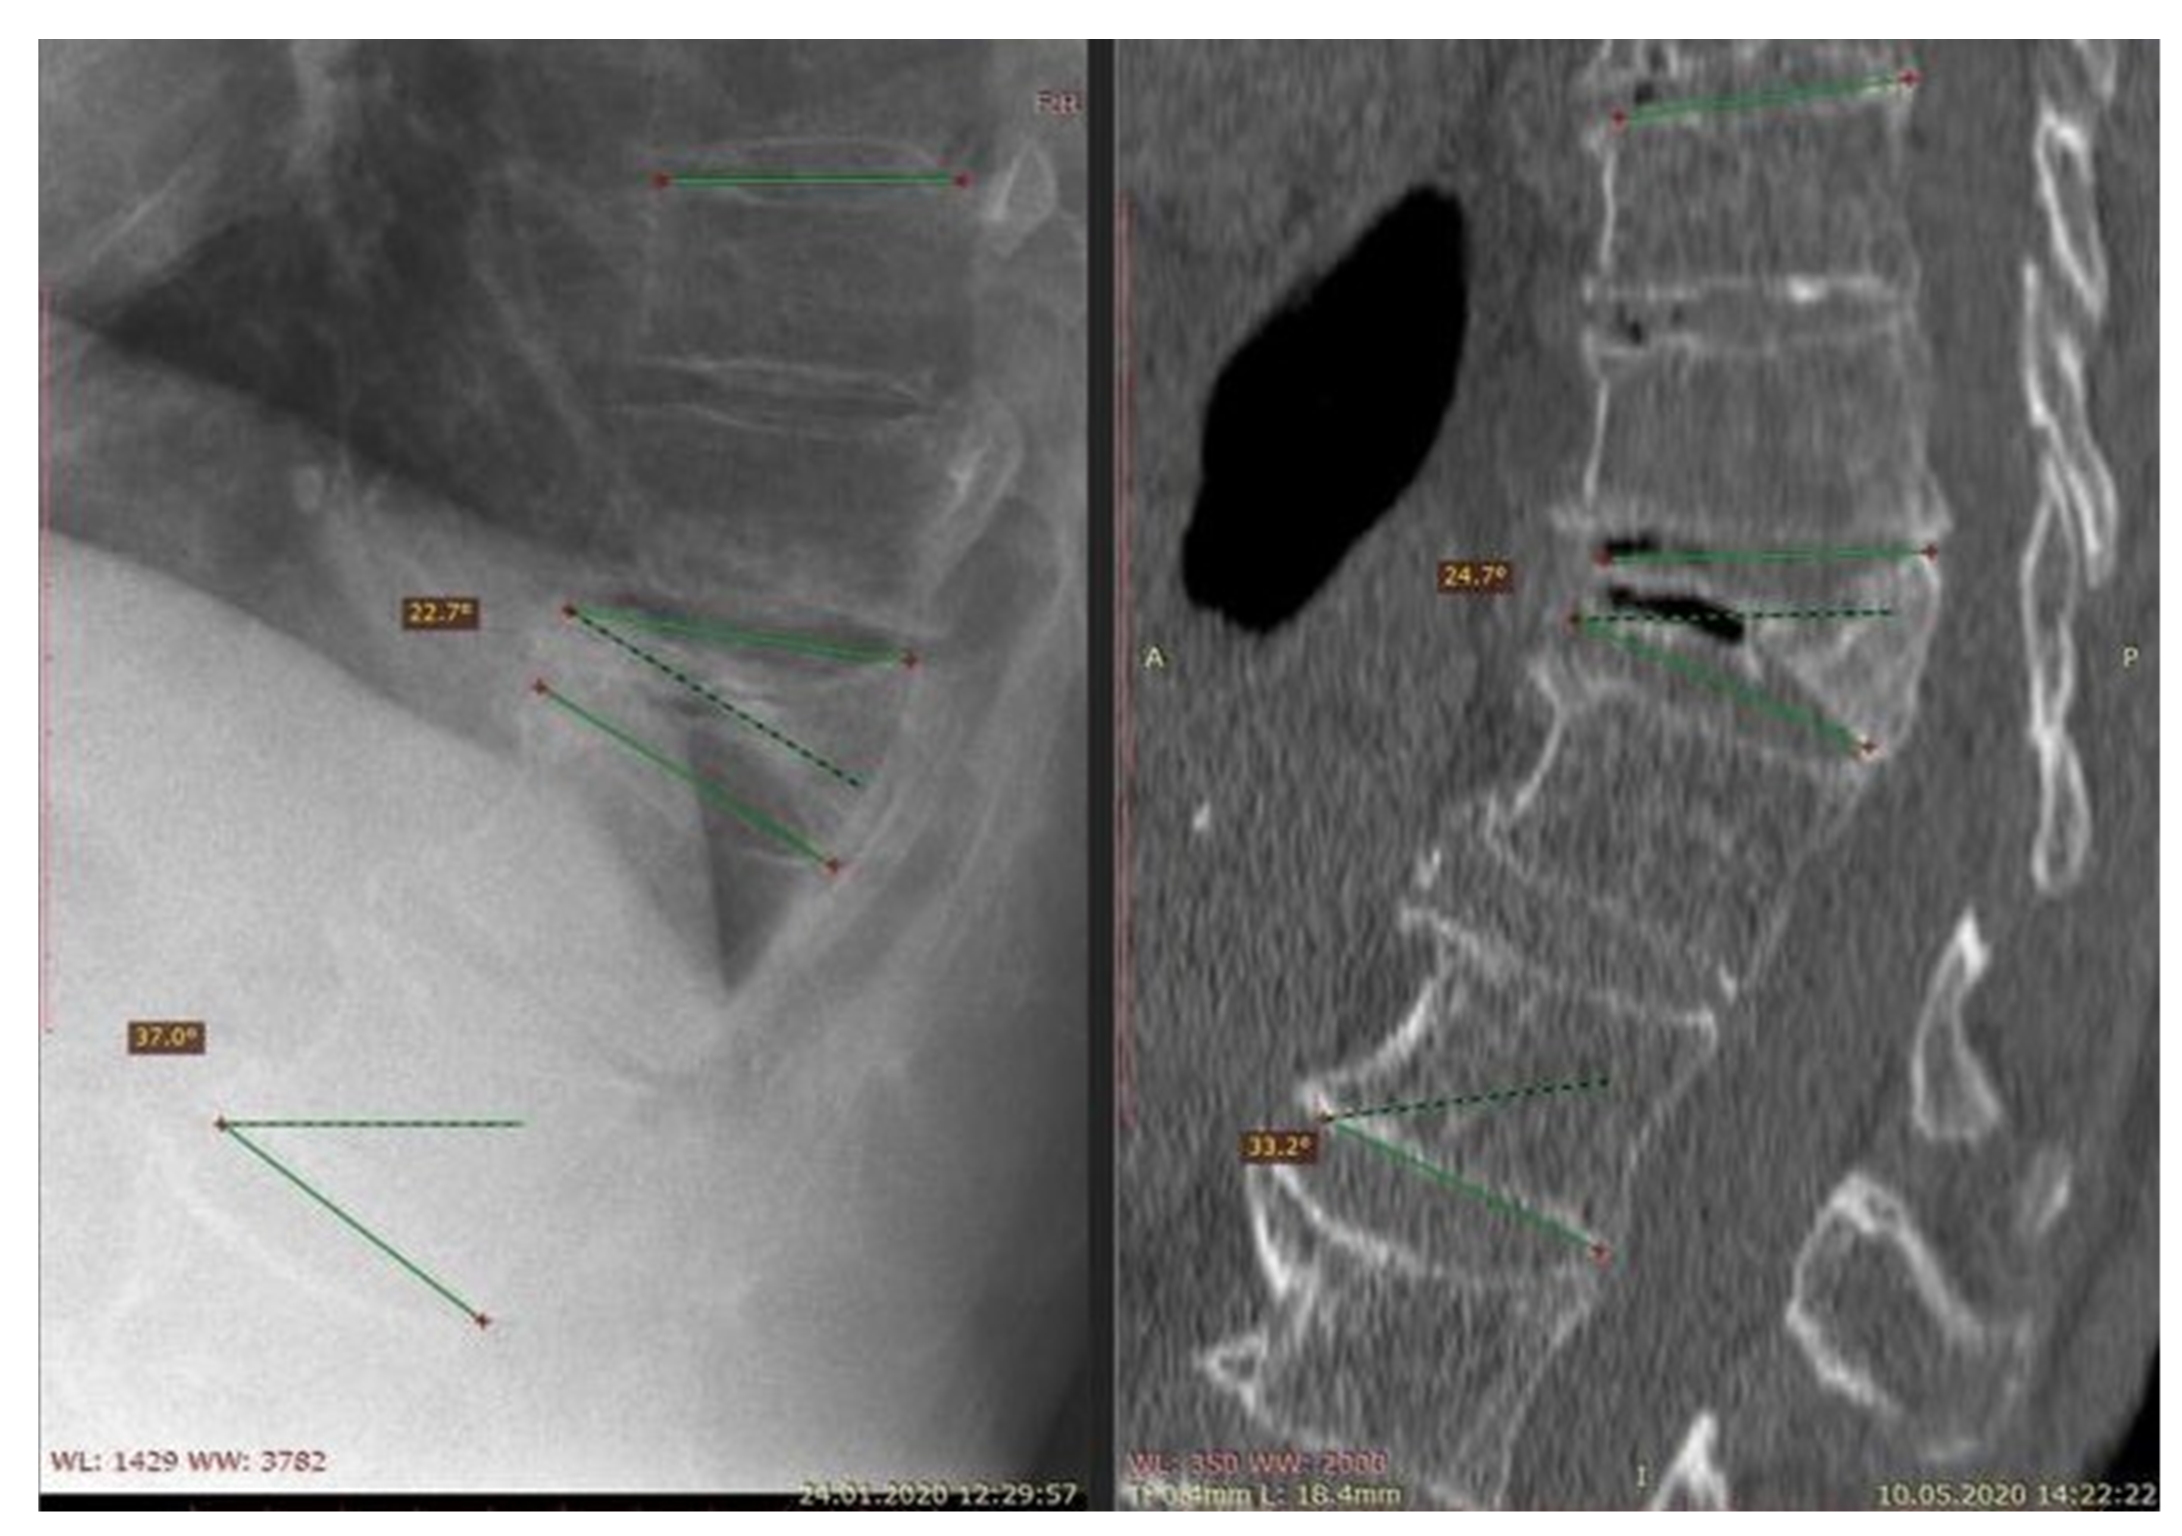

- Adamska, O.; Modzelewski, K.; Stolarczyk, A.; Kseniuk, J. Delayed posttraumatic vertebral body collapse “Kummell disease”. Med. Case Rep. Study Protoc. 2021, 2, e0092. [Google Scholar] [CrossRef]